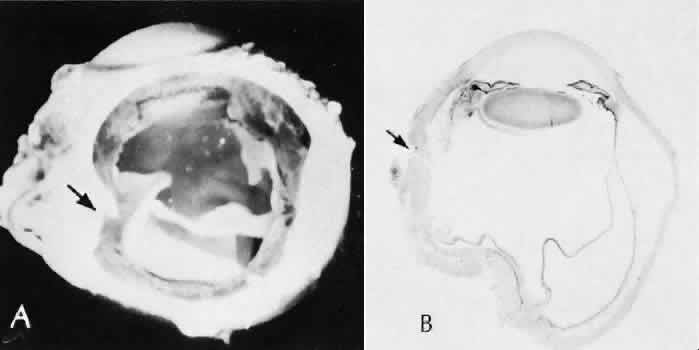

A flat anterior chamber is characterized by anterior displacement of the iris to near or in actual contact with the posterior surface of the cornea. The most common cause is leakage of aqueous along one of the suture tracks. Prolonged decompression of the anterior chamber increases the risk of synechiae formation and intractable secondary closed-angle glaucoma. Corneal endothelial damage may result in bullous keratopathy. Choroidal edema (choroidal hydrops or detachment) (Fig. 31) may be associated with a flat anterior chamber and may potentiate the condition. The choroidal edema will slow or stop aqueous production by the ciliary body, further delaying reformation of the anterior chamber. The histologic characteristics of choroidal edema consist of spreading of the choroidal tissue in a fanlike configuration and eosinophilic fluid filling the intervening spaces. The edema fluid may be lost in processing, leaving multiple apparently empty spaces.

Fig. 31. A case of choroidal detachment. A. By fundus reflex, a large dome-shaped mass can be seen originating from the choroid. The differential diagnosis would include uveal malignant melanoma. In this case, the clinical findings were due to choroidal detachment from the sclera because of fluid accumulating in the suprachoroidal space following cataract surgery. B. The histologic section from another case of choroidal detachment illustrates the location (arrow) and extent of the detachment. In this case the detachment extends to the region of the ciliary body limited anteriorly by the attachment of the choroid to the scleral spur. The displacement of the ciliary body will result in apparent shallowing of the anterior chamber. (Hematoxylin-eosin stain; × 6.)